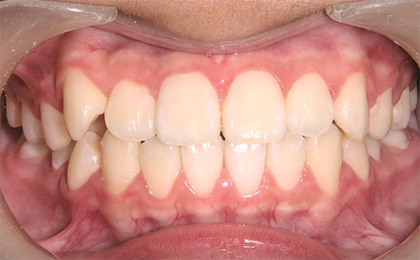

Case1 前歯のガタガタ、部分的な受け口

After

治療内容 | 上のあごに固定式の拡大装置を装着し、あごを拡げてできた隙間で上の前歯のガタガタを治療し、永久歯列に生え変わるまで経過観察を行いました。 |

治療のリスク | 歯の生え変わりにより拡大装置が合わなくなることがあります。 |